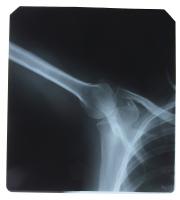

Jakie są powikłania złamania kości?

Czy po złamaniu ręki czy nogi są jakieś powikłania? Ból w miejscu złamania, opuchlizna ? to tylko jeden z nielicznych skutków złamania kości